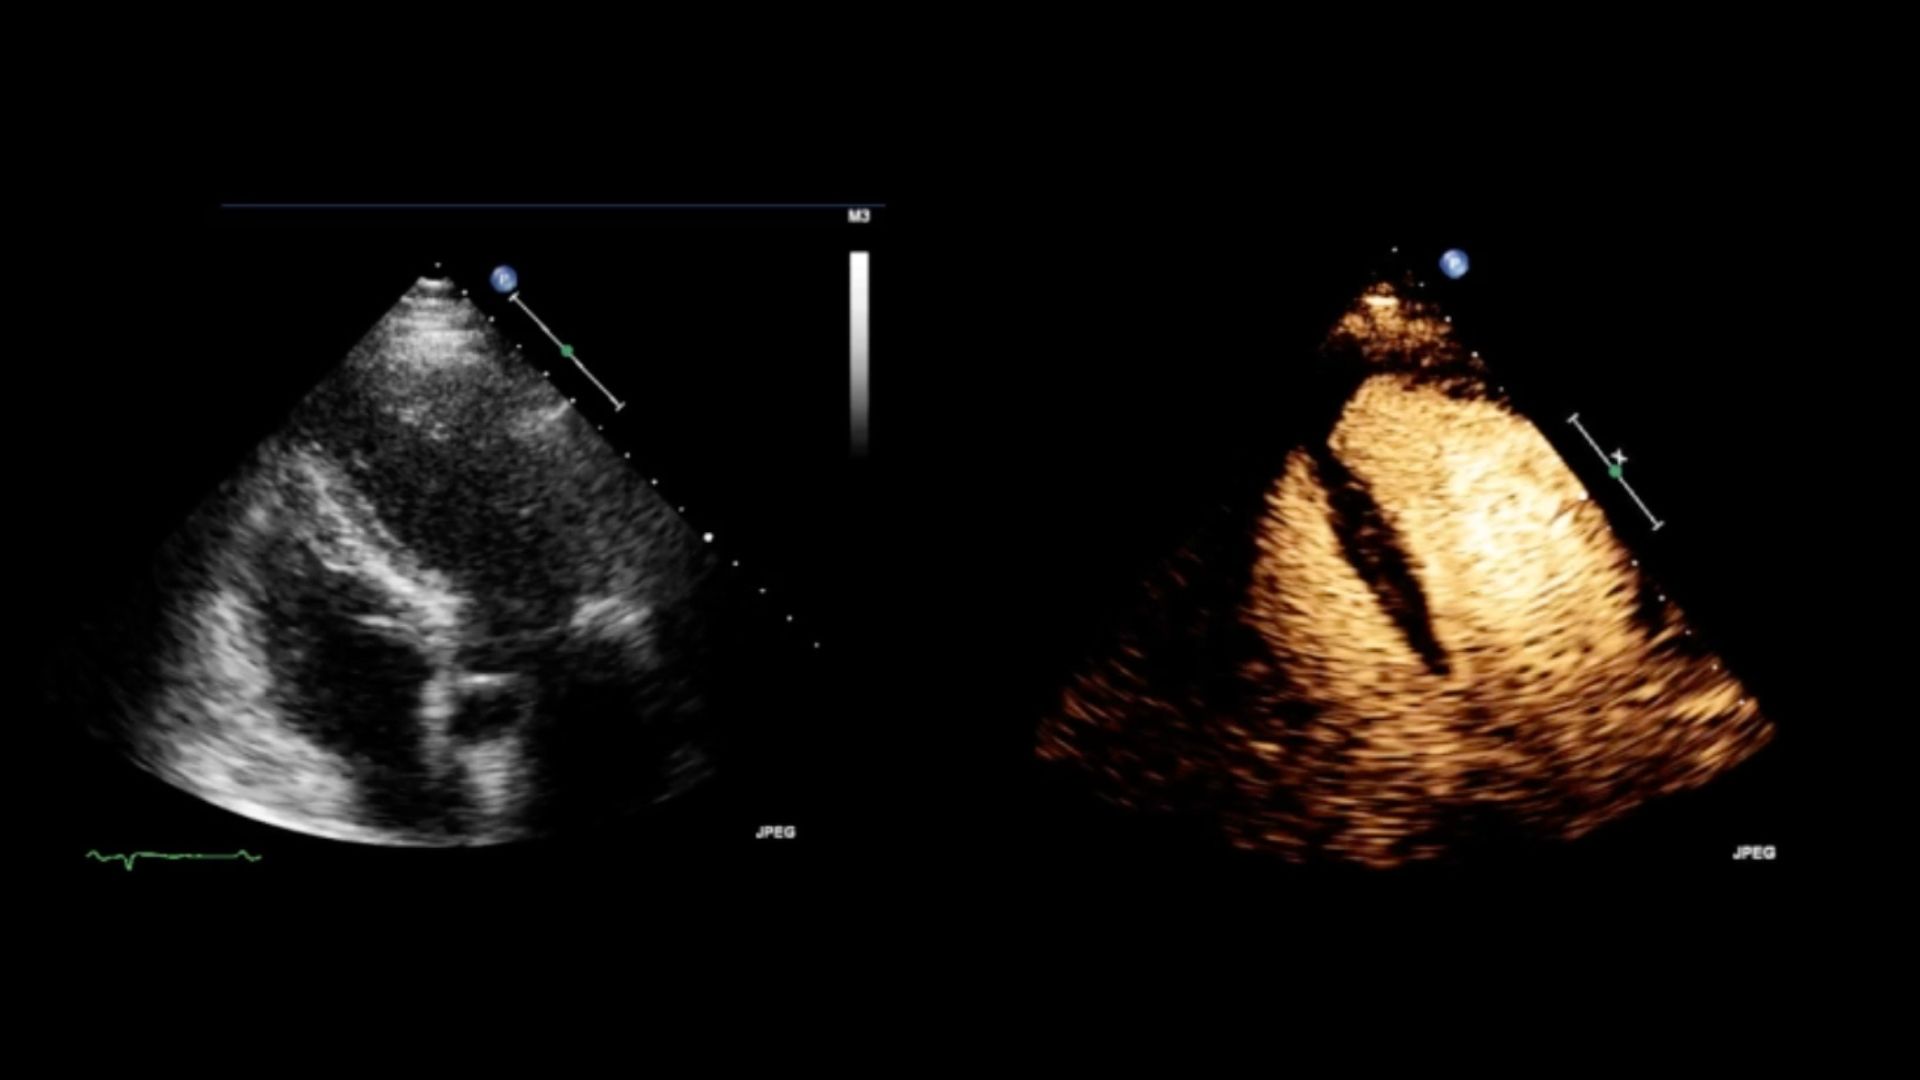

Saps què és una ecocardiografia amb contraste "SonoVue"? Aquí t'ho expliquem!

És la realització d’una ecocardiografia amb administració de contrast endovenós a petició del cardiòleg responsable. Aquesta prova permet millorar la qualitat de les imatges per poder interpretar millor l’estudi cardíac.

El cardiòleg responsable avalua l’administració de contrast endovenós per poder completar la prova. Tot i que es podria finalitzar l’estudi sense administrar-se “SonoVue”, això implicaria que la informació de la malaltia quedaria reduïda.